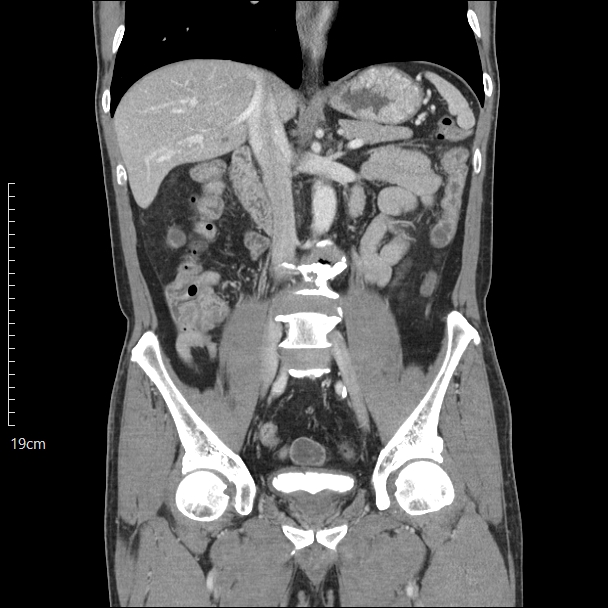

복부 CT(Computed Tomography)는 X-ray를 다양한 각도에서 촬영한 뒤, 컴퓨터로 단면 영상을 재구성해 복부 장기와 구조물을 정밀하게 확인할 수 있는 검사입니다. 일반 X-ray보다 해상도가 높고, 3차원적인 정보 제공이 가능해 응급 진단과 정밀 평가에 널리 사용됩니다.

복부 장기는 서로 밀접하게 위치해 있기 때문에, 구분을 명확히 하기 위해 조영제(요오드계 약물)를 주입하는 경우가 많습니다. 조영제를 통해 혈관, 염증, 종양, 출혈 등을 더 뚜렷하게 확인할 수 있습니다.